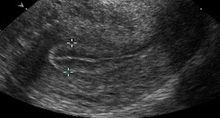

三線征

三線征,子宮內膜與子宮肌層之間形成的高回聲的外側線及兩層子宮內膜表層緊貼形成的清晰可見的高回聲的中心線。